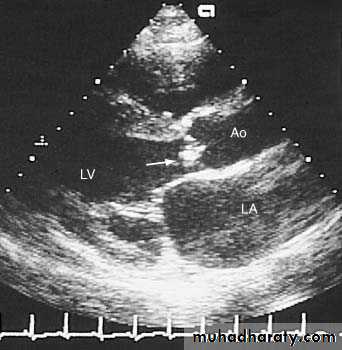

Vegatations on the mitral valve

7

Vegetations on top of mitral stenosis

8

Vegetations on a biologic valve

9